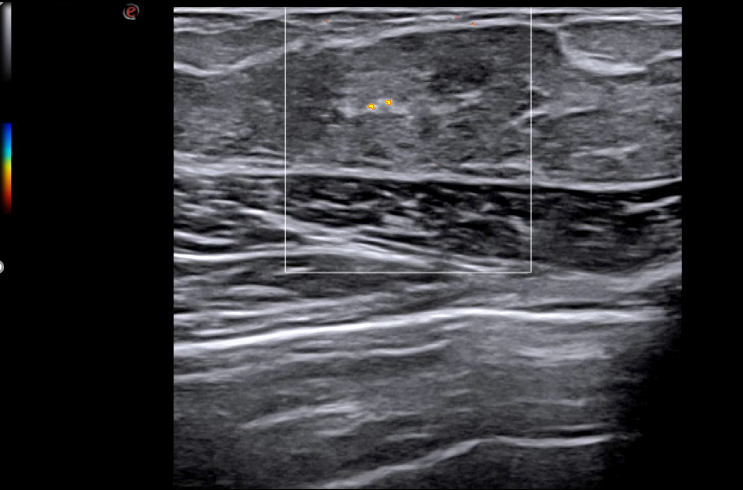

- Supersentiv Doppler og Micro-V

Du ser strukturer tydeligere og mer detaljert enn tidligere. Ultrahøy «framerate» for dynamiske undersøkelser. En super sensitiv og stabil fargedoppler gir en dopplersensitivitet man ikke finner maken til, kombinert med markedets høyeste frekvenser på 25 Mhz. Den nye lineærproben med 4-25Mhz oppløsning, vil bli din nye favoritt. Gir fremragende og markedsledende bildekvalitet på helt overfladiske skanninger, samtidig med premium bildekvalitet ned til 2.5-3.0 cm. Dette er helt enestående for MyLab X90.

Ny bildeoptimaliseringsteknologi; X-View 5.0, fremhever hver eneste piksel, fjerner støy i bildet og forsterker overganger mellom strukturer. Dette gir en utrolig skarphet i bildet og hjelper deg å se hver eneste detalj. M-View 5.0 styrer signalene i flere retninger og legger informasjonen til bildet. Denne utrolige effekten reduserer artefakter og støy i tillegg til å forsterke bildeklarheten. Esaote er kjent for en ekstremt følsom farge – og powerdoppler og leveres nå i tillegg med MicroV. Alle modaliteter kan man styre signalet i ønsket retning, farge og følsomhet. Velg ønsket modul og du vil se mye der du tidligere ikke fikk frem dopplerinformasjon.

MicroV, den nyeste dopplerteknologien fra Esaote med en enestående følsomhet selv i små kar og deteksjon av lave hastigheter. MicroV har en algoritme som helt overlegent separerer bevegelse av væske fra andre bevegelser som skaper forstyrrelser. Dette gir en helt unik dopplerfølsomhet ikke sett tidligere. Med MicroV er det mulig å endre visualiserings algoritmen for å ytterligere forsterke det du ønsker å se.

Kliniske bilder.